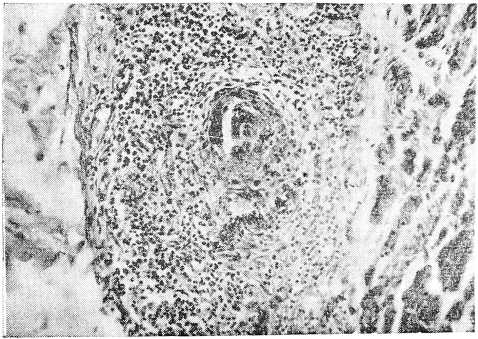

Рис. 1. Гломерулонефрит при болезни Шенлейн—Геноха. Видны увеличенные клубочки, богатые ядрами, образование полулуний. (Ок. 7, об. 8)

Микроскопическое исследование (окраска гематоксилин-эозином, пикрофуксином, на фибрин по Вейгерту): Почки — клубочки значительно увеличены, выполняют просветы капсул, значительно увеличено количество эндотелиальных элементов, обилие лейкоцитов. Плазматическое пропитывание, а местами фибриноидный некроз сосудистых петель клубочков и афферентных сосудов. Пролиферация эпителия капсул Шумлянского — Боумена, местами с образованием полулуний. В просветах капсул встречаются скопления эритроцитов и белковой массы. Зернистая дистрофия эпителия канальцев, в просветах которых скопления эритроцитов. В ин- терстиции—лимфоидные инфильтраты, расположенные преимущественно вокруг клубочков. Сердце- эпикард отечен, разрыхлен с круглоклеточными инфильтратами.. Мелкие артерии и вены эпикарда с пролиферацией адвентициальных и эндотелиальных элементов и сужением просвета. Аналогичные изменения в мелких сосудах миокарда. Стенка тонкой кишки: отек и кровоизляния в подслизистом слое и серозном покрове. Набухание и пролиферация эндотелия капилляров. Местами клеточные муфты вокруг мелких артерий. Кожа: множественные мелкие кровоизлияния, в дерме и подкожной клетчатке. Выраженная пролиферация эндотелия капилляров, мелких артерий и вен. Периваскулярные клеточные инфильтраты, преимущественно из полинуклеаров; последние местами густо инфильтрируют и самую стенку сосудов..

Микроскопическое исследование. Почка — большая часть клубочков увеличена в размерах за счет пролиферации эндотелия и накопления лейкоцитов в просветах сосудистых петель; увеличенные клубочки почти целиком выполняют просветы капсул. Некроз части сосудистых петель. Отдельные клубочки деформированы, имеют лопастную форму, бедны клеточными элементами и частично фиброти- зированы. Отмечается очаговое утолщение капсулы клубочков и образование полулуний. Дистрофия эпителия мочевых канальцев, в просвете их цилиндры и кровь. Набухание и фибриноидный некроз стенки мелких артерий и артериол почки, пролиферация эндотелия. Местами разрастание межуточной соединительной ткани. В интерсти- ции почки видны круглоклеточные и лейкоцитарные инфильтраты, расположенные преимущественно вокруг клубочков и мелких артерий. Местами лейкоциты инфильтрируют стенки мелких артерий, образуя вокруг последних значительные муфты. Сердце: Деструкция стенки мелких артерий и артериол миокарда с разволокнением и набуханием, а местами и фибриноидным некрозом, пролиферацией эндотелия и образованием небольших адвентициальных клеточных муфт. Селезенка: множественные мелкие очажки некроза в пульпе, редукция фолликулов, местами картины эндопериваскулита. Стенка пищевода: небольшие язвы слизистой оболочки. В подслизистом слое и в ад- вентиции пищевода мелкие артерии в состоянии фибриноидного некроза, а местами и полной деструкции с широкими эозинофильными муфтами вокруг них. Резкое умень- щение просвета и утолщение стенки некоторых сосудов, встречаются тромбы в различной стадии организации. Стенка кишки: обширные кровоизлияния в подслизистом и мышечном слоях, местами пропитывание кровью всей стенки, пролиферация эндотелия капилляров с почти полным стиранием их просвета. Пролиферация эндотелиальных клеток и адвентициальных элементов стенки мелких артерий и вен. Встречаются периваскулярные лейкоцитарные инфильтраты.